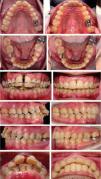

DIAGNOSISMesofacial patient, with convex profile (Figure 1), skeletal class II due to retrognathism (Table I), molar and canine class II, over-erupted incisors with severe upper and lower dental proclination, increased overjet, diastema, triangular arches (Figures 2 and 3) and widespread loss of alveolar ridges, mainly in the upper central incisors (Figure 4).

0.022” x 0.028” MBT fixed appliances (3M UNITEK, Monrovia, CA) were placed. Through height control during placement of the upper and lower anterior brackets, incisor over-eruption was corrected. Aligning and leveling of the arches was performed using 0.014” and 0.016” Nickel Titanium round arches. Subsequently, 0.016” x 0.022” rectangular arches of the same alloy and 0.016” x 0.022” stainless steel were used. Due to the existence of black triangles, it was decided to remodel the triangular anatomy of the upper and lower front teeth by performing interproximal reduction. Posterior anchorage segments were formed (linked in block from canine to molar) and subsequently proceeded to close the created spaces with elastic string from canine to canine. Incisal ameloplasty of the edges of the upper incisors was also conducted in order to improve aesthetics (Figure 5).

Fixed appliances were removed and fixed retainers were bonded from canine to canine in both arches (Figure 6). Use of circumferential removable retainers (upper and lower) was indicated 24hours a day.

TREATMENT RESULTSThe existent defect between the upper central incisors was significantly reduced; however, due to its severity and extension, it could not be corrected entirely (Figures 7 to 10). The rest of the treatment goals were achieved in a satisfactory manner; however, the class II molar and canine relationship was not resolved in its entirety due to the fragility of the periodontal tissues (Table II).

The patient was very satisfied with the obtained aesthetics; masticatory function was improved as well as the teeth stability. The integrity of the periodontal tissues was optimized (Figures 11 to 15).